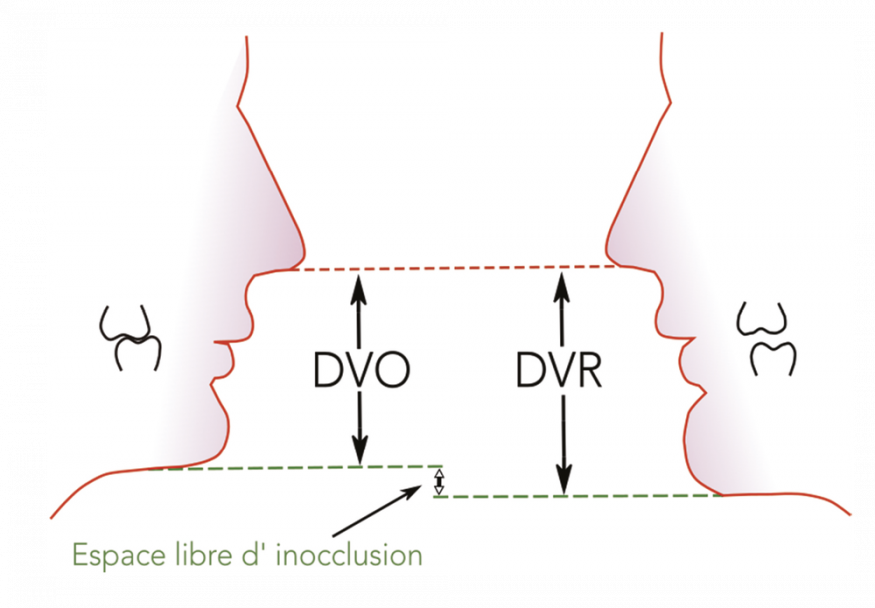

La DVO existe chez le denté : elle est stable, constante et reproductible, étant assurée par le calage occlusal. Chez l’édenté total, la DVO n’existe plus et on ne peut mesurer cliniquement que la dimension verticale de repos (DVR), correspondant en moyenne à la DVO à laquelle on soustrait la valeur de l’espace libre d’inocclusion (ELI), tel que DVO = DVR – ELI (fig. 1a-b).

Estimation de l’ELI (fig. 17)